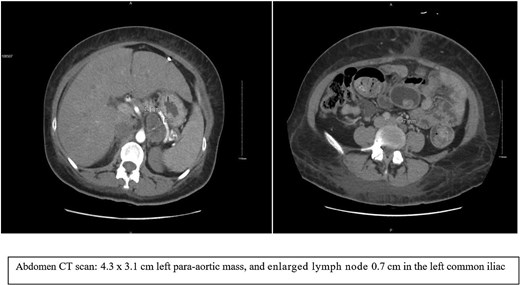

MRI as shown in (Fig. 2), a 2.2 × 4.5 × 3.5 cm well-defined, mostly separable left para-aortic mass from the spleen and pancreas, arising from the left adrenal gland. It is hypointense on T1, heterogeneously hyperintense on T2, with slow enhancement, mild diffusion restriction, central calcification, and necrosis—no invasion into adjacent structures. Differential diagnoses include ganglioneuroma and hemangioma. Further positron emission tomography (PET/CT) is recommended to confirm benignity and rule out adrenocortical carcinoma.

MRI images showed a well-defined left para-aortic mass that mostly arises from the left adrenal gland.